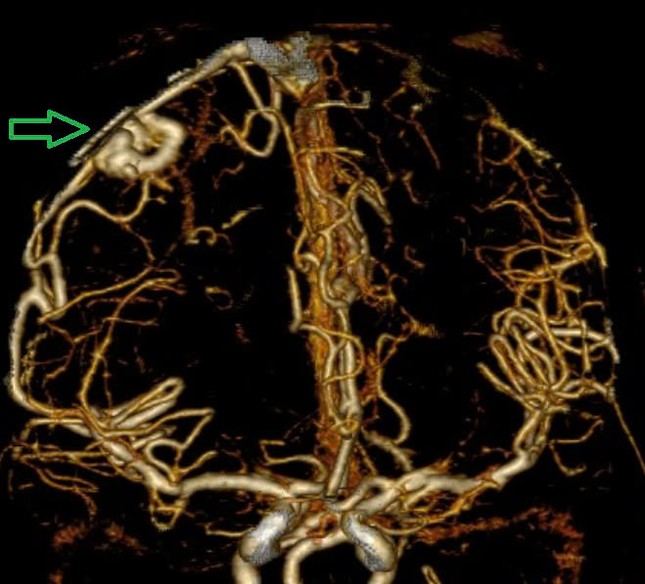

Hình ảnh chụp MSCT mạch não: Chảy máu não thuỳ đỉnh phải, chảy máu não thất do vỡ AVM ( điểm Spetzler Martin 2 điểm) bệnh nhân nữ, 29 tuổi. Ảnh: Bệnh viện Bạch Mai

Trường hợp thứ ba : Nữ bệnh nhân 29 tuổi, tiền sử khoẻ mạnh. Bệnh nhân đến viện vì đột ngột đau đầu, tê tay, nôn nhiều vật vã. Tại bệnh viện tỉnh, bệnh nhân được chẩn đoán chảy máu não, các bác sĩ đã đặt ống nội khí quản thở máy rồi chuyển tuyến lên Trung tâm Đột quỵ, Bệnh viện Bach Mai trong tình trạng ý thức hôn mê, Glasgow 6 điểm, thở máy, đồng tử bên phải giãn 4mm, tụt huyết áp, duy trì vận mạch. Chụp MSCT mạch não: Chảy máu não thuỳ đỉnh phải, chảy máu não thất do vỡ AVM ( điểm Spetzler Martin 2 điểm). Bệnh nhân đã được phẫu thuật lấy máu tụ và khối dị dạng. Tuy được điều trị tích cực nhưng di chứng để lại vô cùng nặng nề. Sau một tháng điều trị, bệnh nhân chưa nhận thức được, liệt hoàn toàn nửa người trái…